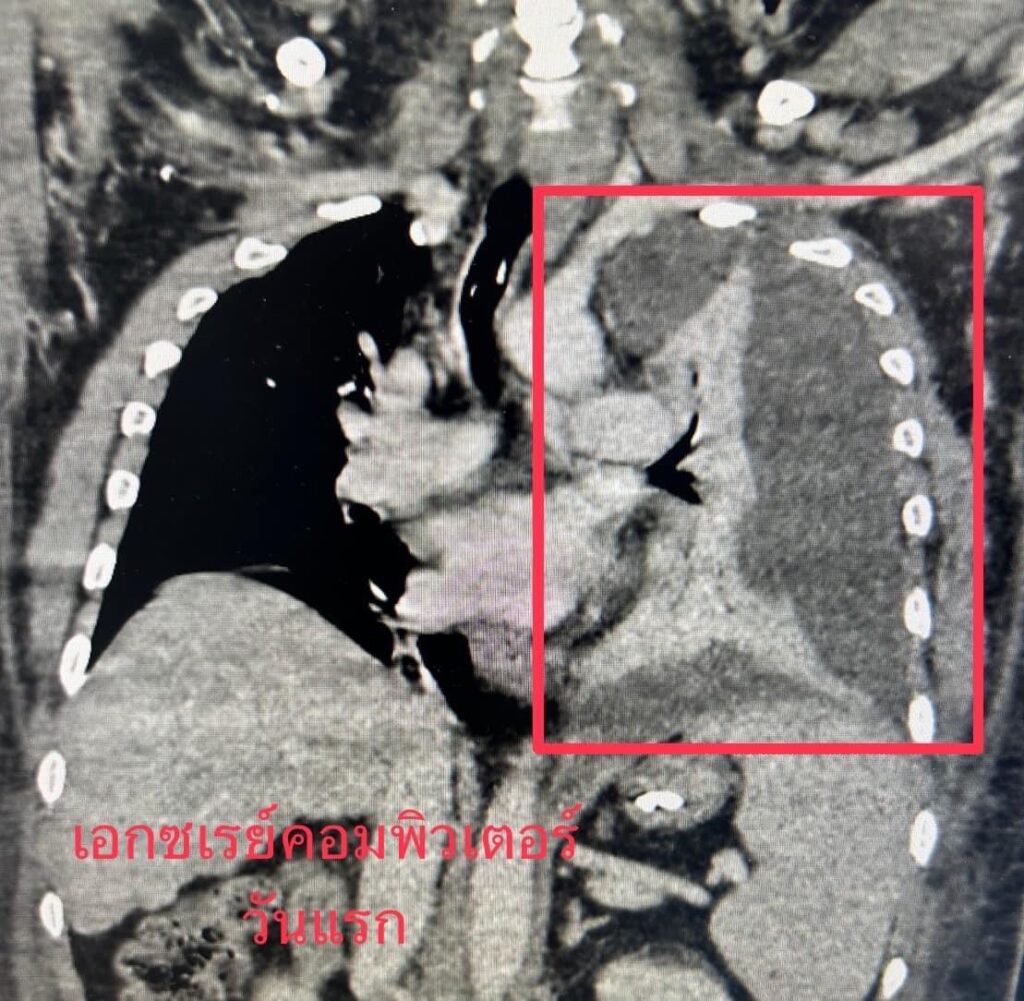

หมอพบเคสชวนอึ้ง!! ผลเอ็กซเรย์ปอดซ้ายหายเกือบหมด! เจาะมาเจอหนองสีน้ำตาล

ผู้ป่วยน่าสนใจ เป็นผู้ป่วยชายอายุ 40 ปีเศษ น้ำหนัก 103 กิโลกรัม มีประวัติดื่มหนัก และมีโรคประจำตัวเป็นเบาหวาน ให้ประวัติเจ็บหน้าอกซ้าย เป็นเวลา 3 วัน ต่อมาเริ่มมีไข้สูง ไอ เหนื่อยหอบ หายใจไม่สะดวก ญาตินำส่งโรงพยาบาล

แพทย์ที่รับตัวขณะแรกรับนำผู้ป่วยเข้าเอกซเรย์ปอด ผลเอกซเรย์ปอดซ้ายหายไปเกือบทั้งหมด ผู้ป่วยเริ่มมีความดันต่ำ ชีพจรเบา หัวใจเต้นเร็ว หายใจเร็ว กระสับกระส่าย เริ่มไม่รู้สึกตัว แสดงถึงอาการช็อกจากระบบการหายใจล้มเหลว แพทย์ต้องรีบใส่ท่อหายใจ นำเข้าไอซียู เจาะปอดซ้ายพบว่ามีน้ำหนองสีน้ำตาล มีกลิ่นเหม็น จึงทำการผ่าตัดใส่ท่อระบายหนองเป็นการด่วน สามารถระบายหนองออกมาประมาณ 1,200 cc. ส่งเพาะเชื้อ ระหว่างนั้นแพทย์ให้ยาต้านเชื้อในทันที ที่คาดว่าจะคลุมเชื้อที่พบได้บ่อย

ทั้งนี้ แพทย์ได้ใส่ท่อช่วยหายใจ และใช้เครื่องช่วยหายใจพยุงการหายใจให้ปกติ ปรึกษาแพทย์ศัลยศาสตร์ทรวงอก เพื่อพิจารณาผ่าตัดเพิ่มเติม หากการระบายหนองออกจากปอดไม่ได้ผล

อย่างไรก็ตาม วันที่ 3 หลังใส่ท่อระบายหนอง พบว่าคนไข้ปอดขยายตัวได้ดี อีก 7 วันต่อมาหนองไม่ออกเพิ่ม แพทย์จึงเอาท่อระบายหนองออก ไข้ลดลง สัญญาณชีพปกติ ปอดขยายตัวกลับมาเกือบปกติ ถอดท่อหายใจและเครื่องช่วยหายใจออกได้ โดยผู้ป่วยกลับมาหายใจได้เป็นปกติ

เคสนี้หมออารักษ์ เปิดเผยว่า ได้เร่งฟื้นฟูสภาพปอด ควบคุมเบาหวาน และรักษาภาวะตับไม่ปกติ ซึ่งเป็นสาเหตุทำให้ภูมิคุ้มกันต่ำ ติดเชื้อในช่องเยื่อหุ้มปอด เกือบเอาชีวิตไม่รอด